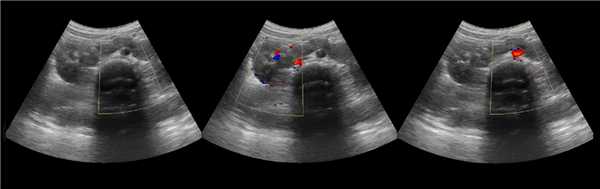

Рисунок. У новорожденного на УЗИ почек определяется гидронефроз (1) и расширенный мочеточник (2) справа. В мочевом пузыре двустороннее уретероцеле (3). При исследовании левой почки структурных изменений не выявлено.

Рисунок. На УЗИ определяется удвоенная чашечно-лоханочная система, расширена лоханка верхнего сегмента (1) и мочеточник на всем протяжение (2, 3), в мочевом пузыре уретроцеле (4). Полное или неполное удвоение чашечно-лоханочной системы возможно увидеть с помощью КТ-урографии.

Рисунок. Дистальный отдел мочеточника расширен, в мочевом пузыре анэхогенное образование с тонким и ровным контуром — уретероцеле.

Рисунок. Двустороннее уретероцеле на УЗИ: в режиме ЦДК из верхушек уретероцеле определяется выброс мочи.

Рисунок. На УЗИ в уретероцеле определяется гиперэхогенная структура с акустической тенью — камень. Уретероцеле может являться одним из факторов, способствующих камнеообразованию.